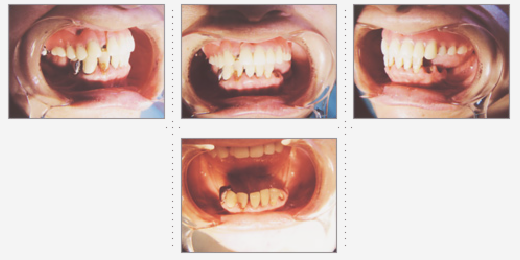

症例2

主婦 33才 女性

上下顎とも乳歯が残っており歯と歯の隙間が気になり、歯並びを奇麗にしたいとのご希望でした。

術後、家族や友人からもキレイになったと言われ、ご本人もご自分の歯のように気に入っていただけました。原因不明な頭痛もなくなり、快適な生活を送っていらっしゃいます。